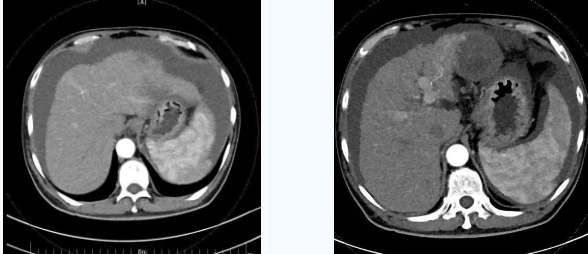

術(shù)后一個(gè)月秦先生來(lái)院復(fù)查,腹水已明顯較前減少,精神和飲食較術(shù)前明顯好轉(zhuǎn)。

韓國(guó)宏院長(zhǎng)介紹,TIPS原理是采用特殊的介入治療器械,在X線透視導(dǎo)引下,經(jīng)頸靜脈入路,建立肝內(nèi)的位于肝靜脈及門靜脈主要分支之間的人工分流通道,并以金屬覆膜內(nèi)支架維持其永久性通暢,達(dá)到降低門脈高壓后減少腹水產(chǎn)生,控制和預(yù)防食道胃底靜脈曲張破裂出血的目的。